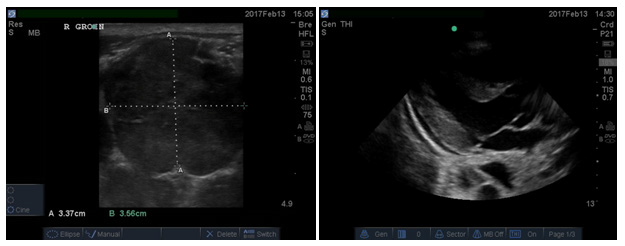

The patient had multiple huge adenopathies localized on cervical region, subclavical region, both axillar, and on both groins. Bed site Ultrasound findings: multiple lymph nodes of neck and para-auricular, cervical, axillar, and inguinal regions. The biggest measuring 3-5 cm. He also had huge ascitis, bilateral pleural effusion, and small pericardial effusion. Initial laboratory results were showing mild elevated white blood cell (24.15), with normal differentiation Hemoglobin of 8.3g/dl; renal, liver function test, and electrolytes were normal. The following are bed site ultrasound images (Figures 2-7). Based on history, physical exam and Ultrasound images, we can conclude that swelling is lymph nodes and not anything else. Our differential diagnoses were Hodgikin lymphoma. To rule out TB adenitis, the internal medicine consultant requested a fine needle aspiration (FNA), which was none conclusive, and the pathologist suggested doing an open biopsy. The results of open biopsy showed: HL Hodgkin lymphoma (Nodular sclerosis type). Nodular sclerosis Hodgkin's disease accounts for 80% of all Hodgkin's disease.2

Figure 4 & 5 Right groin Lymph node & Pericardial effusion.

Figures 6 & 7 Ascitis & Neck Lymph Node.